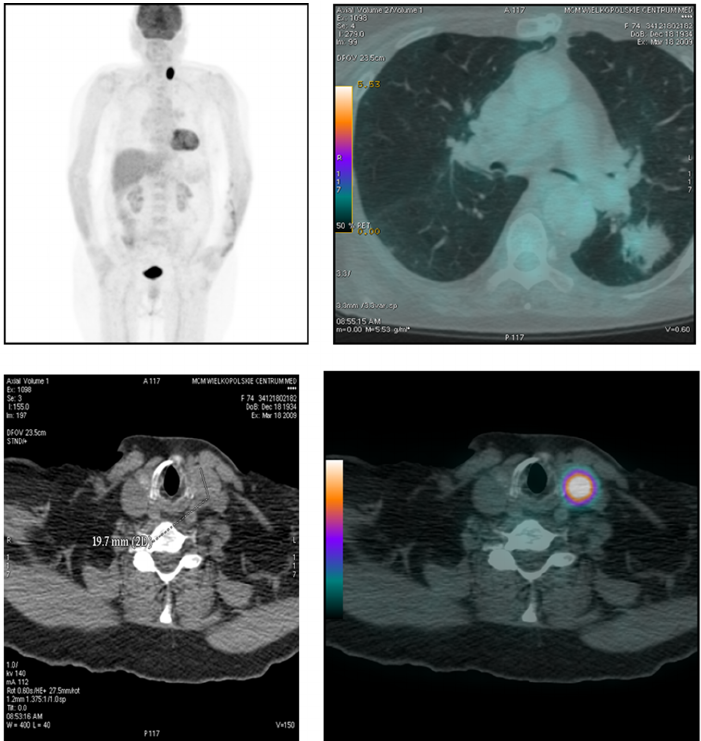

NRRD(Nearly Raw Raster Data)是一种用于存储类似于热图成像数据的文件格式。其实我们可以将NRRD看作为类似于bitmap之类的未压缩的原始光栅图像文件。只要我们有对应的解码方式,我们就可以像查看普通图片文件一样查看NRRD文件。

在上面所提到的线性变化转换过程,其实就是一个热图绘制的过程。我们一般按照不同的颜色谱做线性变换映射,就可以得到对应的不同颜色系列下的NRRD热图成像渲染结果。对于NRRD图像文件的热图成像渲染原理,其实是和质谱成像的渲染原理一摸一样的(对于质谱成像渲染而言,其主要的原理也就是将对应的扫描点上的目标离子的intensity值取出,构建出一个和NRRD文件中的光栅矩阵数据一摸一样的矩阵数据,基于这个矩阵数据进行线性变换映射到对应的颜色值完成热图成像可视化操作)。

那现在我们很轻松的基于R#脚本就拥有了从NRRD文件之中所读取出来的光栅矩阵数据之后,如果我们需要将得到光栅矩阵数据进行可视化,该怎样做呢?其实,如果我们了解过热图成像或者质谱成像的原理的话,实际上对于这个光栅矩阵的原始数据进行成像的原理应该就会很清楚了。在我们拿到这个矩阵之后,可以将矩阵的行和列看作为二维图像空间之中的x和y坐标信息,然后对应的矩阵中的单元格值可以映射为一个对应的颜色,即可将从NRRD文件之中拿到的光栅矩阵数据给可视化出来。将光栅矩阵中的数值映射为对应的颜色值的方法原理,大家可以参考一下《【热图数据可视化】颜色插值计算原理》的内容介绍,一摸一样。

对于一个三维扫描的数据,其最本质上仍然是基于二维的矩阵堆叠出来的。如果我们需要将其某一断层显示出来,那么我们可以通过函数获取特定断层的栅格矩阵数据,然后按照相同的热图成像的方式就可以绘制出来了。getRasterLayer